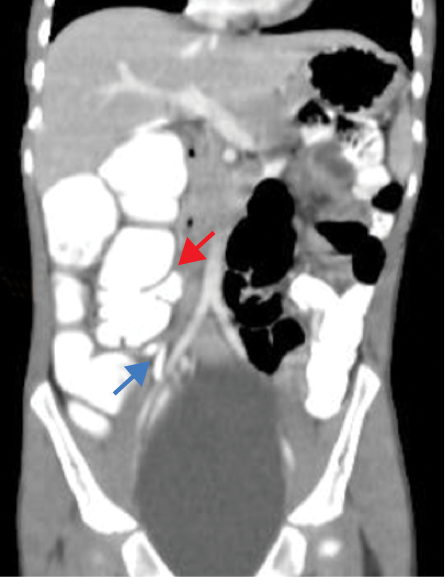

The contrast-enhanced computed tomography (CECT) abdomen findings were as follows: The D3 segment of the duodenum was seen to cross to the left side with the duodeno-jejunal junction in its expected location. The superior mesenteric arter-superior mesenteric vein (SMA-SMV) relationship was maintained with the SMV lying on the right side of SMA. The small bowel loops were predominantly on the left side of the abdomen, and the entire colonic loops were positioned on the right side of the abdomen [Figure 1]. The ileocecal junction (ICJ), cecum, and appendix were noted in the right lumbar region [Figure 2]. The inferior mesenteric artery was seen coursing to the right side of the midline, rather than its normal left-sided course [Figure 3]. A tubular cystic lesion was observed in relation to the small bowel loops on the left side of the abdomen [Figure 4]. Intrabdominal solid organs were essentially normal, with a normal situs.

Figure 1: Coronal sections of the contrast-enhanced computed tomography scan of the abdomen, showing the abnormal positioning of the small bowel loops on the left side (red arrow), and the large bowel loops on the right side (blue arrow), suggesting the possibility of hindgut malrotation.